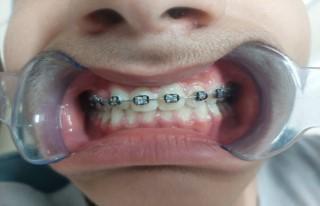

Γ4. Ελεγχος ανατολής κυνοδόντων και διάνοιξη υπερώας (ref.15,16)

Κατά την εξέλιξη του ανθρωπίνου είδους οι γνάθοι γίνονται μικρότεροι. Για αυτόν τον λόγο και οι φρονιμίτες, τρίτοι γομφίοι, γίνονται συνήθως έγκλειστοι, καθώς και οι άνω κυνόδοντες που ανατέλλουν προτελευταίοι στην άνω γνάθο και δεν βρίσκουν αρκετό χώρο στα οδοντικά τόξα.

Στα 7 χρόνια του παιδιού εξετάζουμε με πανοραμική ακτινογραφία τη θέση των μονίμων άνω κυνοδόντων στο οστό και αναλόγως πράττουμε.

Αν δεν υπάρχει αρκετός χώρος για αυτά,κάνουμε διεύρυνση της υπερώας με ορθοπεδικό μηχάνημα.

024 Με

να ανατείλουν και έτσι αποφεύγουμε μελλοντικό εγκλεισμό τους στο οστό της άνω γνάθου. Έγκλειστος κυνόδοντας σε ενήλικα, παρουσία του νεογιλού προγόνου του. Η σημασία της στοματικής υγιεινής και ορθοδοντικής πρόληψης

τον τρόπο αυτό τα βοηθάμε

Ορθοδοντική παρέμβαση στον συγκεκριμένο ενήλικα, μετά από χειρουργική αποκάλυψη του εγκλείστου κυνόδοντα, και μεταφορά του στο οδοντικό τόξο.

Για αποφυγή της παραπάνω διαδικασίας τονίζεται ξανά η σημασία του έγκαιρου ορθοδοντικού ελέγχου στην σχολική ηλικία των παιδιών για τη διάγνωση